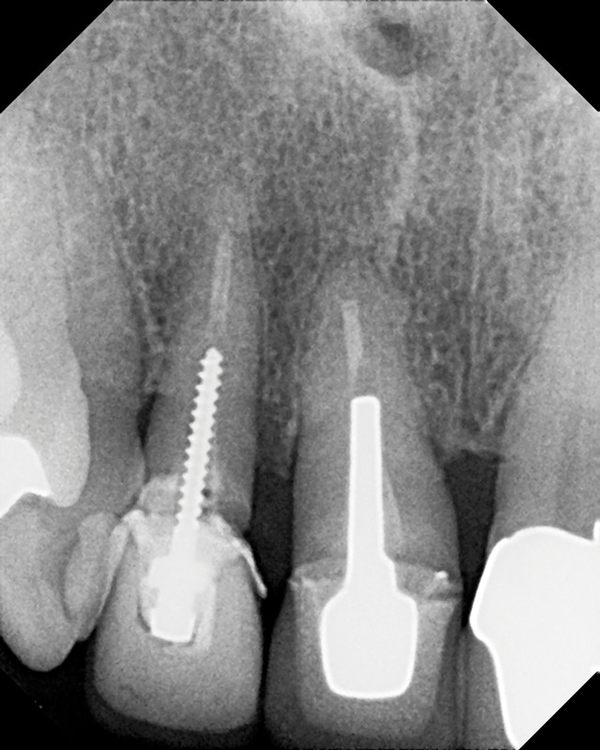

(4.) Radiograph of a root fracture that occurred at the end of a parallel metal post.

Figure 4